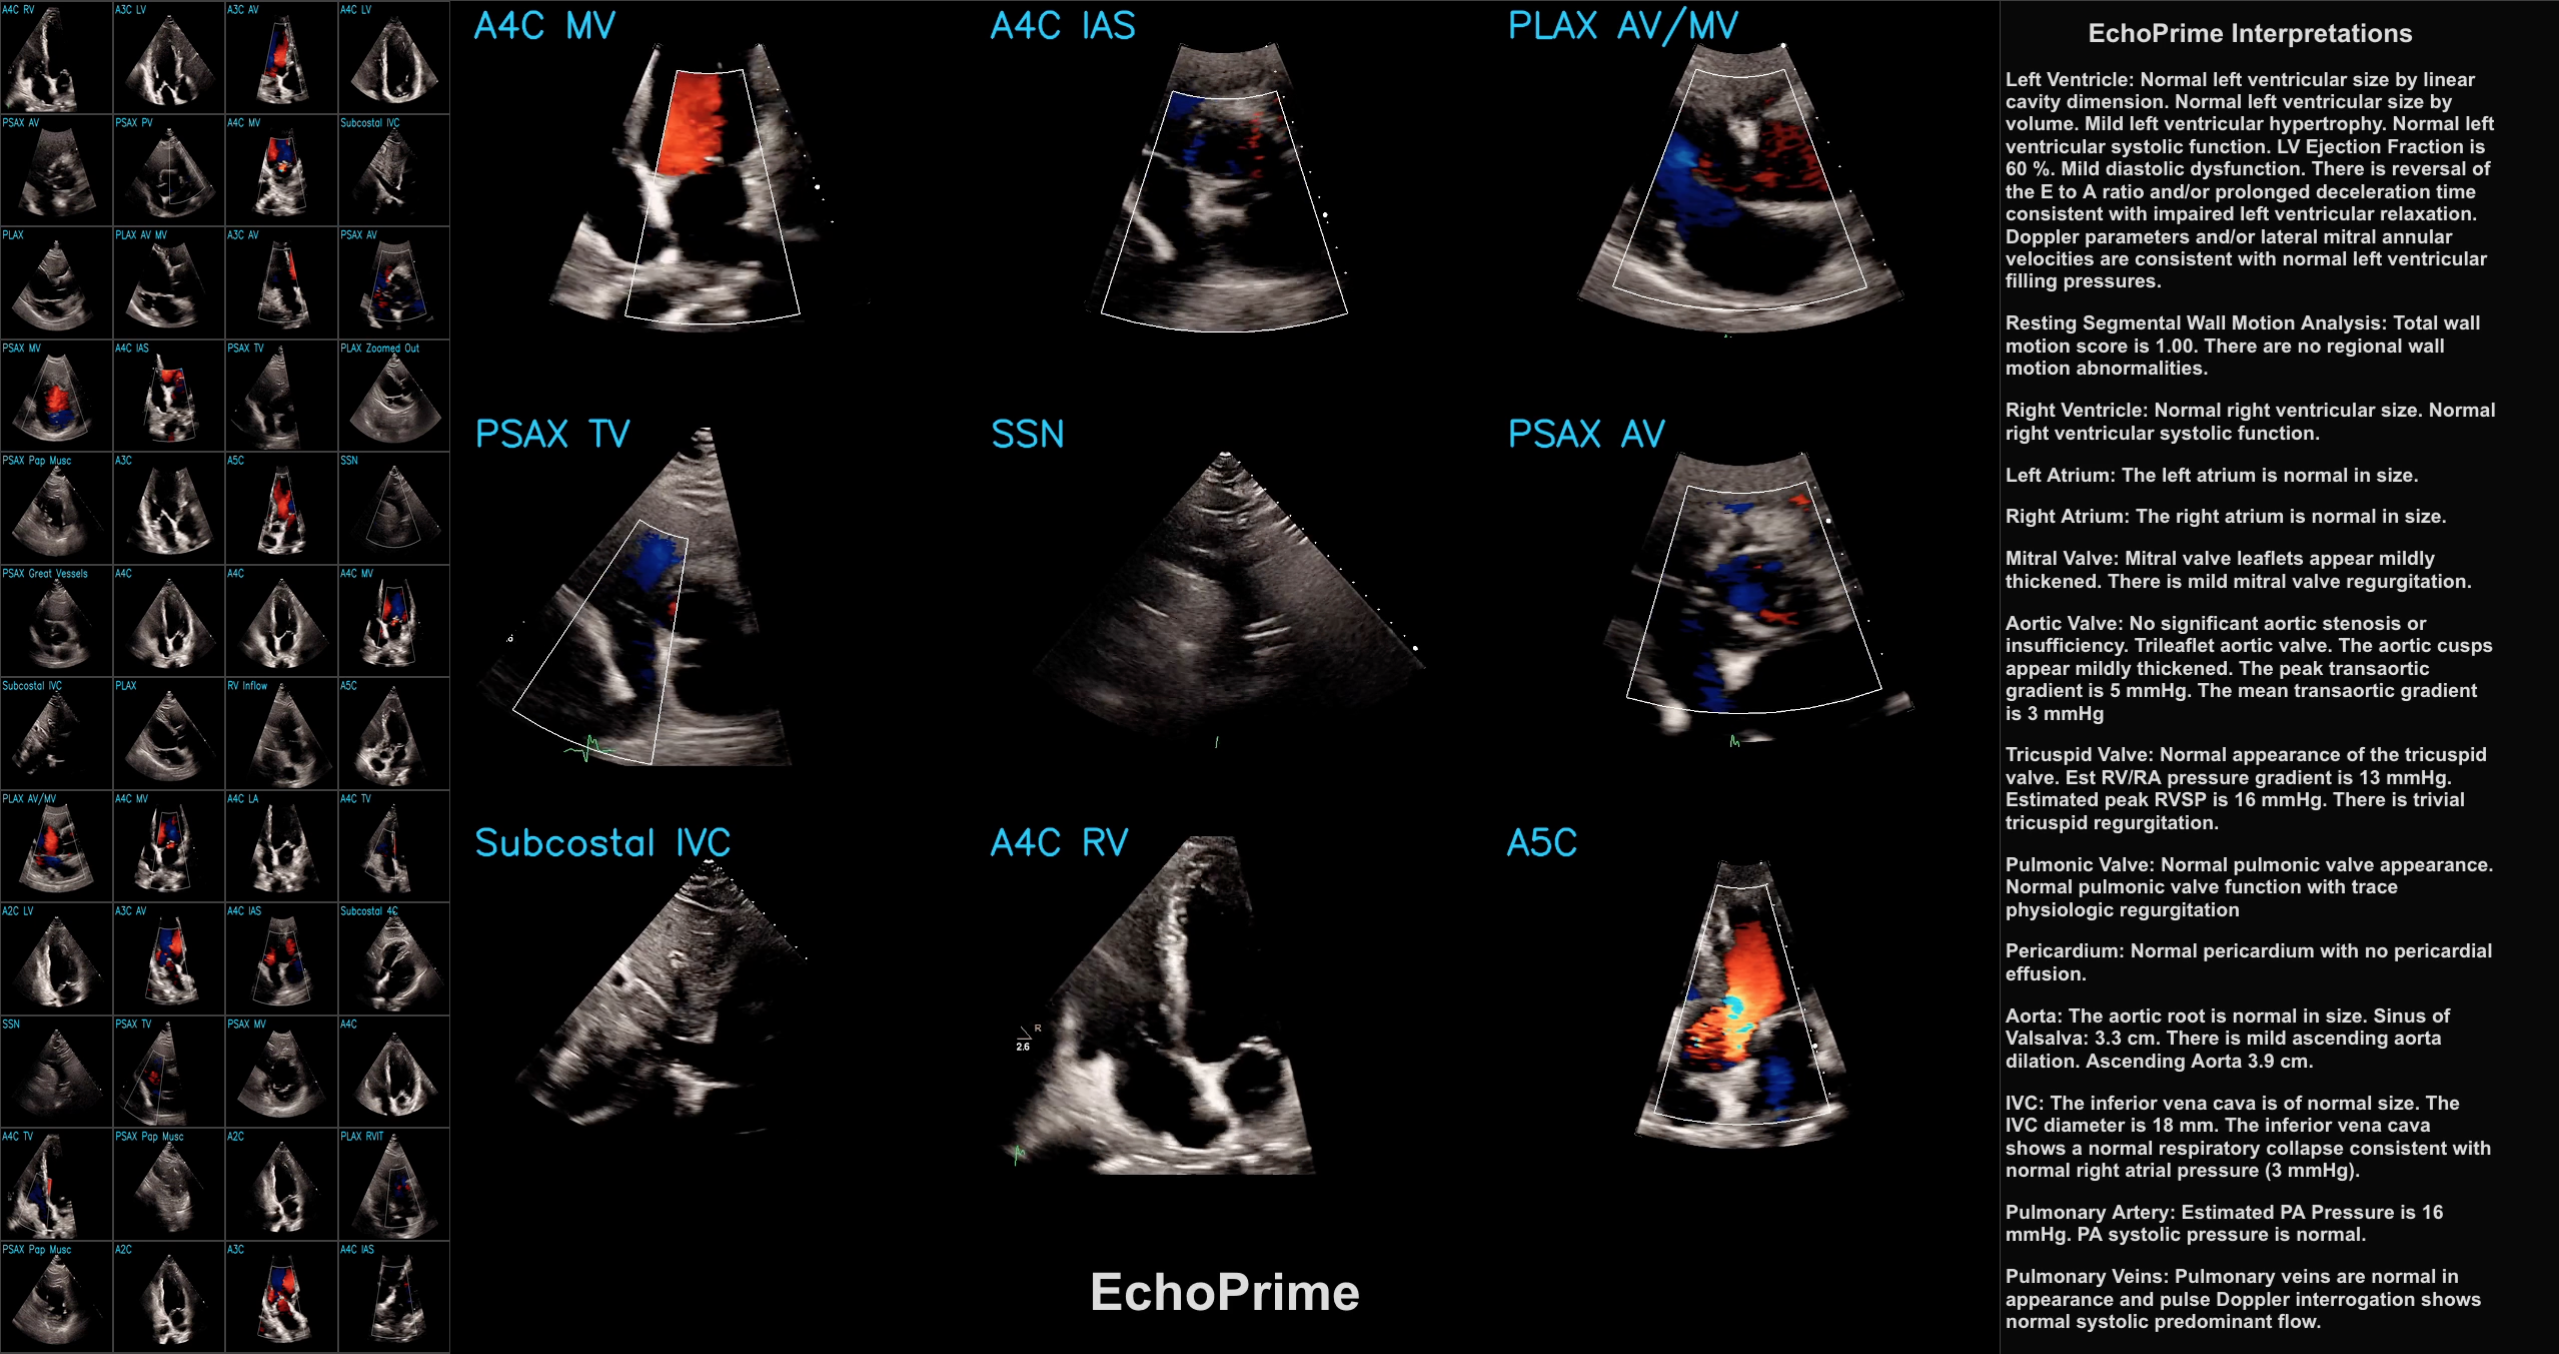

Deep Dive into EchoPrime

Medical AI

This post is a code-forward deep dive into EchoPrime, a multi-video, view-informed Vision-Language Model designed for comprehensive echocardiography interpretation. The code…